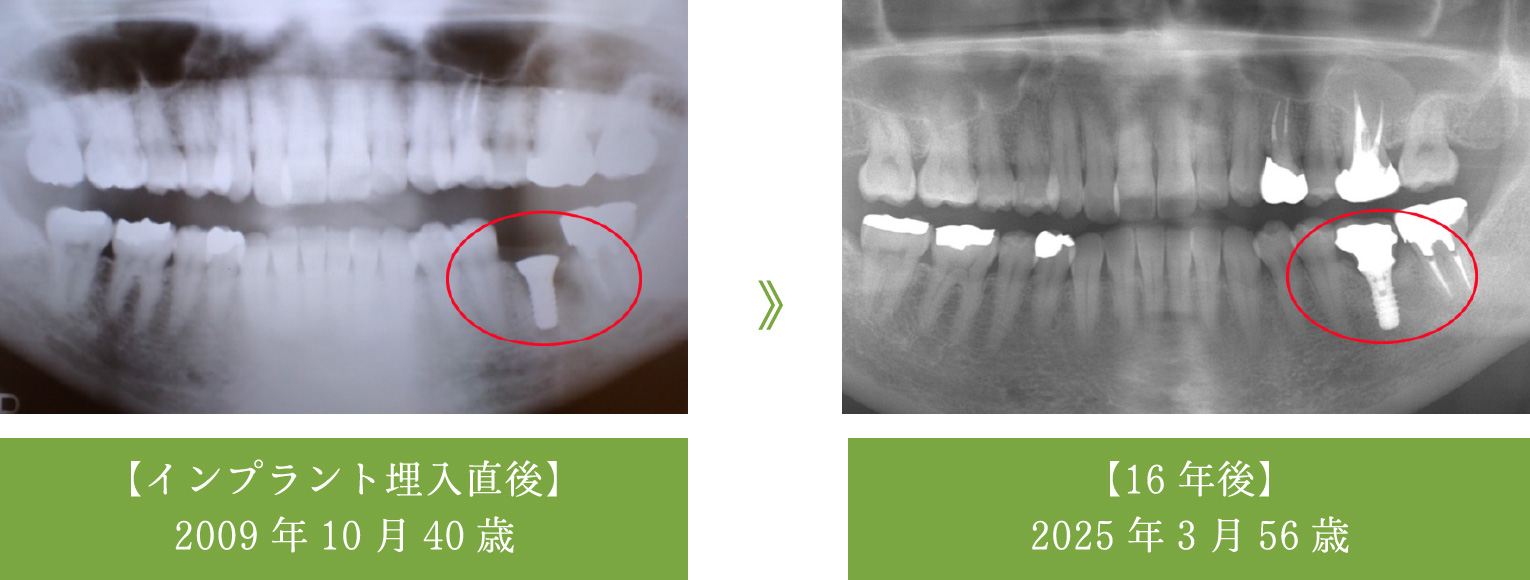

インプラントの16年経過症例-1

【60代で治療→80代現在も良好】他の歯を守るインプラント

- 歯根破折により右下の奥歯を喪失

- インプラント2本を埋入し、しっかりと噛めるブリッジを作製

- 治療から16年経過し、83歳となられた現在もトラブルなく機能しています。

インプラントがしっかりと噛む力を支えているため、この16年間、他のご自身の歯を一本も失うことなく過ごされています。 - メンテナンス

- 3~4ヶ月ごとに歯科衛生士によるパウダークリーニングを実施

- 期間:5ヶ月(12回)

- 費用:88万円(当時の価格/インプラント手術 44万円)

(インプラント2本埋入、被せ物 44万円)

- リスク:術後の腫れ(ピークは3日目程度)、全身疾患の有無確認が必要